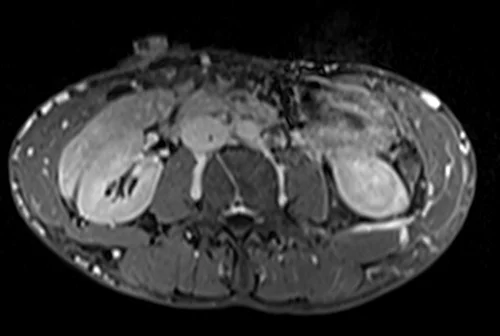

MRV abdomen axial t1 flash post contrast image 6 - MRI